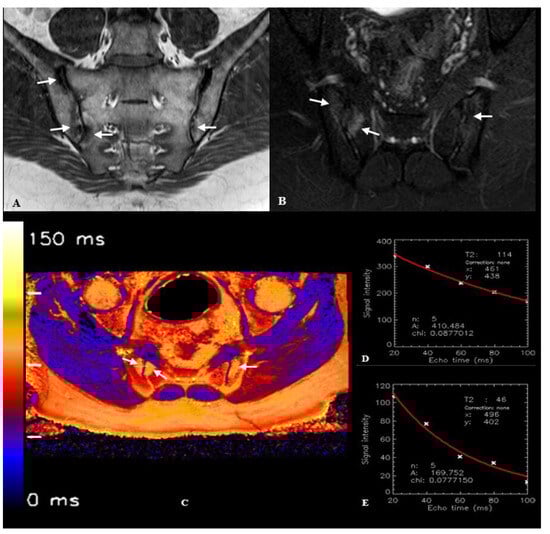

| T2 relaxation time—bone (ms) *, (Mean ± SD) | 100.23 ± 7.41 | 69.44 ± 4.37 | <0.001 |

| T2 relaxation time—cartilage (ms) **, (Mean ± SD) | 44.0 ± 3.19 | 43.2 ± 3.41 | 0.249 |